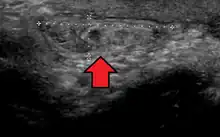

- Tibialis anterior hernia: can present as a bulge in the shins. Pain on rest, walking, or during exercise may occur. The bulge can typically not be present unless pressure or flexing of the leg occurs.[31][32][33]

- ↑ Sharma N, Kumar N, Verma R, Jhobta A (2017-05-31). "Tibialis Anterior Muscle Hernia: A Case of Chronic, Dull Pain and Swelling in Leg Diagnosed by Dynamic Ultrasonography". Polish Journal of Radiology. 82: 293–295. doi:10.12659/PJR.900846. PMC 5462483. PMID 28638493.